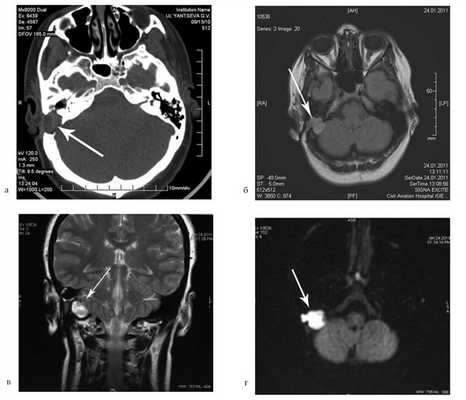

На КТ височных костей справа послеоперационная полость, заполненная мягкотканным образованием, определяется большой костный дефект в направлении сигмовидного синуса и мозжечка (рис. 2, а). Рисунок 2. КТ и МРТ височных костей больной У. с хроническим правосторонним средним отитом. Состояние после радикальной операции (1993 г.), санирующей операции с мастоидопластикой и тимпанопластикой (2003 г.). Холестеатома. Парез лицевого нерва. а — КТ; б — МРТ основания черепа в режиме Т1; в — в режиме Т2; г — в режиме non-EPI DWI.

Больной была выполнена МРТ (рис. 2, б—г).

В режимах Т2 и non-EPI DWI определяется сигнал высокой интенсивности, в режиме Т1 — низкоинтенсивный сигнал. Это может свидетельствовать о наличии холестеатомы мастоидальной полости и пирамиды височной кости. Диагноз: хронический правосторонний средний отит; состояние после радикальной операции в 1993 г. и санирующей операции с мастоидопластикой и тимпанопластикой в 2003 г.; холестеатома; парез лицевого нерва.

Больной произведена санирующая реоперация, в ходе которой удалена холестеатома больших размеров, заполняющая отшнурованную послеоперационную полость. Эта полость распространялась до верхушки сосцевидного отростка, граничила с твердой мозговой оболочкой и достигала верхушки пирамиды височной кости. Полость облитерирована. В послеоперационном периоде получен хороший функциональный результат. Ухо толерантно к воде, не было обострений, гноетечения, головокружений. Сохранилась кондуктивная тугоухость I степени. МРТ через 9 мес подтвердила отсутствие холестеатомы.